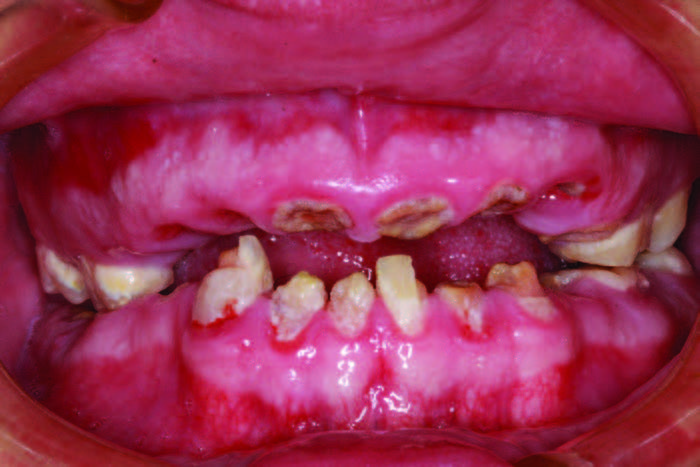

A 26-year-old male was diagnosed with hydrocephaly in utero. Hydrocephalus is a condition where there is an excessive accumulation of cerebral spinal fluid around the brain. Individuals affected with hydrocephalus often have impaired cognitive and physical development.[1,2] He was born into a loving family, but when his mother passed away from cancer, his father was unable to take care of a son with emotional and learning disabilities. This young man went on to have a terminal dentition due to poor oral habits. His grandparents stepped in and have been as supportive as possible, even while he has been living in a group home. They requested a treatment plan that would allow their grandson, whose teeth had been ravaged by soda, the dignity of having his smile replaced with implants. The patient’s Mountain Dew habit had destroyed his smile and self-esteem (Figure 1). The patient’s chronic soda habit with a lack of oversight at his group home led to gross generalized caries. Figure 2).